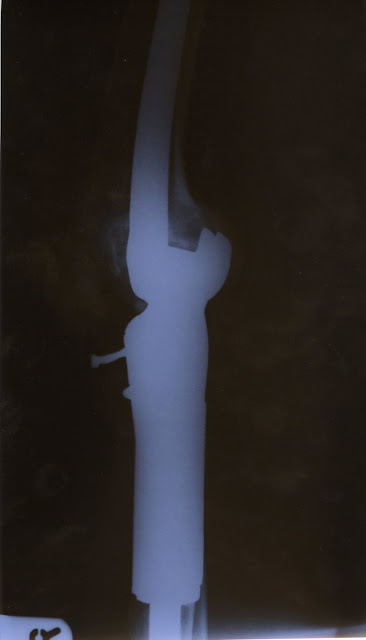

As I kind of loved my leg and wanted to save it I chose to go with the limb salvage option. This involved replacing my diseased bone in my leg with what was known as a Kotz prosthesis.

Following this surgery I had 11 years of sheer hell. Constant infections, tissue breaking down in open wound sites around the screw you can see sticking out on the X-ray and unbelievable pain. Eventually my leg began to become stiffer and stiffer until it was practically permanently in a fixed extended position.